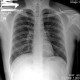

Alodok.. Izin berdiskusi dok hasil radiologi pasien Tn. F, laki-laki, 22 thn keluhan: batuk >2 minggu, batuk berdahak disertai darah + hanya saat pagi hari, demam -, bb turun -, keringat malam hari -, sesak -, nyeri dada -, mual - , muntah -

Pemeriksaan: Rhonki (-/-) - Wheezing (-/-)

kalau dilihat dari hasil cxr nya apakah mengarah ke bronchitis dok? terimakasih 🙏🏻

Pada foto rontgen thorax kesan terdapat multiple kavitasi, yang dapat mengarah ke DD TB paru, bronkiektasisPada pemeriksaan fisik dapat dicari apakah terdapat limfadenopati multiple

Pada pemeriksaan penunjang dapat ditambahkan lab darah seperti darah lengkap dan LED, sputum TCM (bila memungkinkan)

Selain itu, dapat dilengkapi juga faktor resiko pasien lainnya seperti riwayat paparan TB, paparan asap (merokok, lingkungan kerja) yang dapat Semoga dapat membantu 🙏

Alo dokter, saya rasa x foto yang terlihat bersih dok, jika masih tidak membaik dirujuk saja dok ke dokter spesialis paru dokter, cmiiw